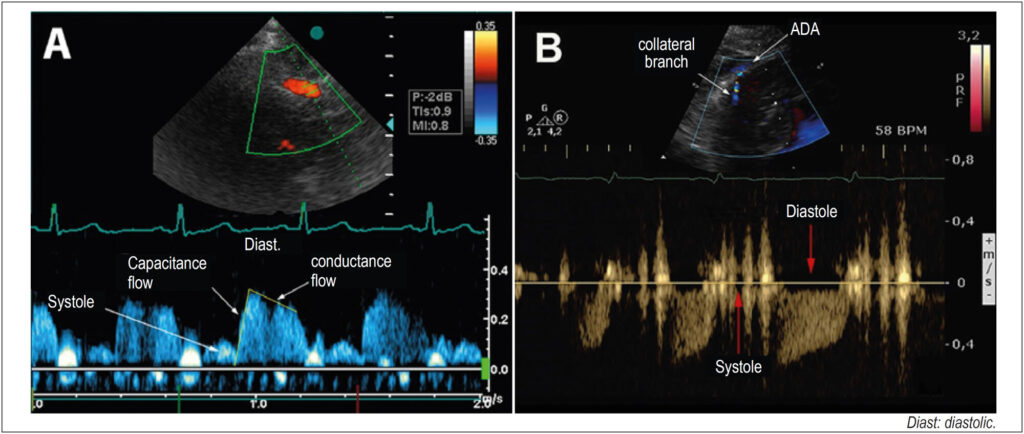

Coronary flow with a diastolic predominance increases two to five times in hyperemia, mediated by vasodilation (coronary flow reserve, CFR) and, in hypertrophy, relative ischemia may occur. In secondary hypertrophy (LVH), the flow, normal at rest, becomes ischemic due to increased demand. In hypertrophic cardiomyopathy (HCM) with perivascular fibrosis, collateral vessels appear to increase the irrigation of hypertrophied segments.

Coronary flow was evaluated in 34 patients with secondary hypertrophy, 24 with hypertrophic cardiomyopathy and in 16 controls. The anterior descending artery was detected with transthoracic Doppler with adequate equipment calibration. In the hypertrophic cardiomyopathy group, the flow of collaterals from the hypertrophic region was evaluated. In the control and secondary hypertrophy groups and in six patients in the hypertrophic cardiomyopathy group, the intravenous dipyridamole (0.84 mg) coronary flow reserve was calculated. The data were compared by variance with a significance of 5%.

In secondary hypertrophy there was an increase in mass index and blood pressure, and in hypertrophic cardiomyopathy an increase in relative thickness predominated. Ejection fraction and diastolic dysfunction were higher in the hypertrophic cardiomyopathy group. The coronary flow reserve was lower in the hypertrophic cardiomyopathy group, and flow of collaterals was also detected, with a reduction in the coronary flow reserve.

the analysis of coronary circulation with transthoracic Doppler is possible in normal and hypertrophic individuals. Patients with secondary hypertrophy and hypertrophic cardiomyopathy have a decrease in the coronary flow reserve, and patients with hypertrophic cardiomyopathy show a hyper flow of dilated collateral vessels observed in the hypertrophic region, with a decrease in the coronary flow reserve.